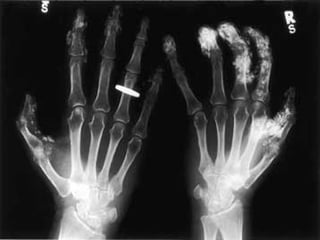

Hand of the patient

A 55 year old man presents with painful swollen mcp joints. His x rays are shown below

The correct answer is   D .  Gout .   The x ray shows large  erosions  which have eaten away the bone both in and around the joint. The involvement is assymetrical which is typical for gout.

A 55 yearold man presents with painful swollen mcp joints. His x rays are shown below

The correct answeris  D . Gout . The x ray shows large erosions which have eaten away the bone both in and around the joint. The involvement is assymetrical which is typical for gout.